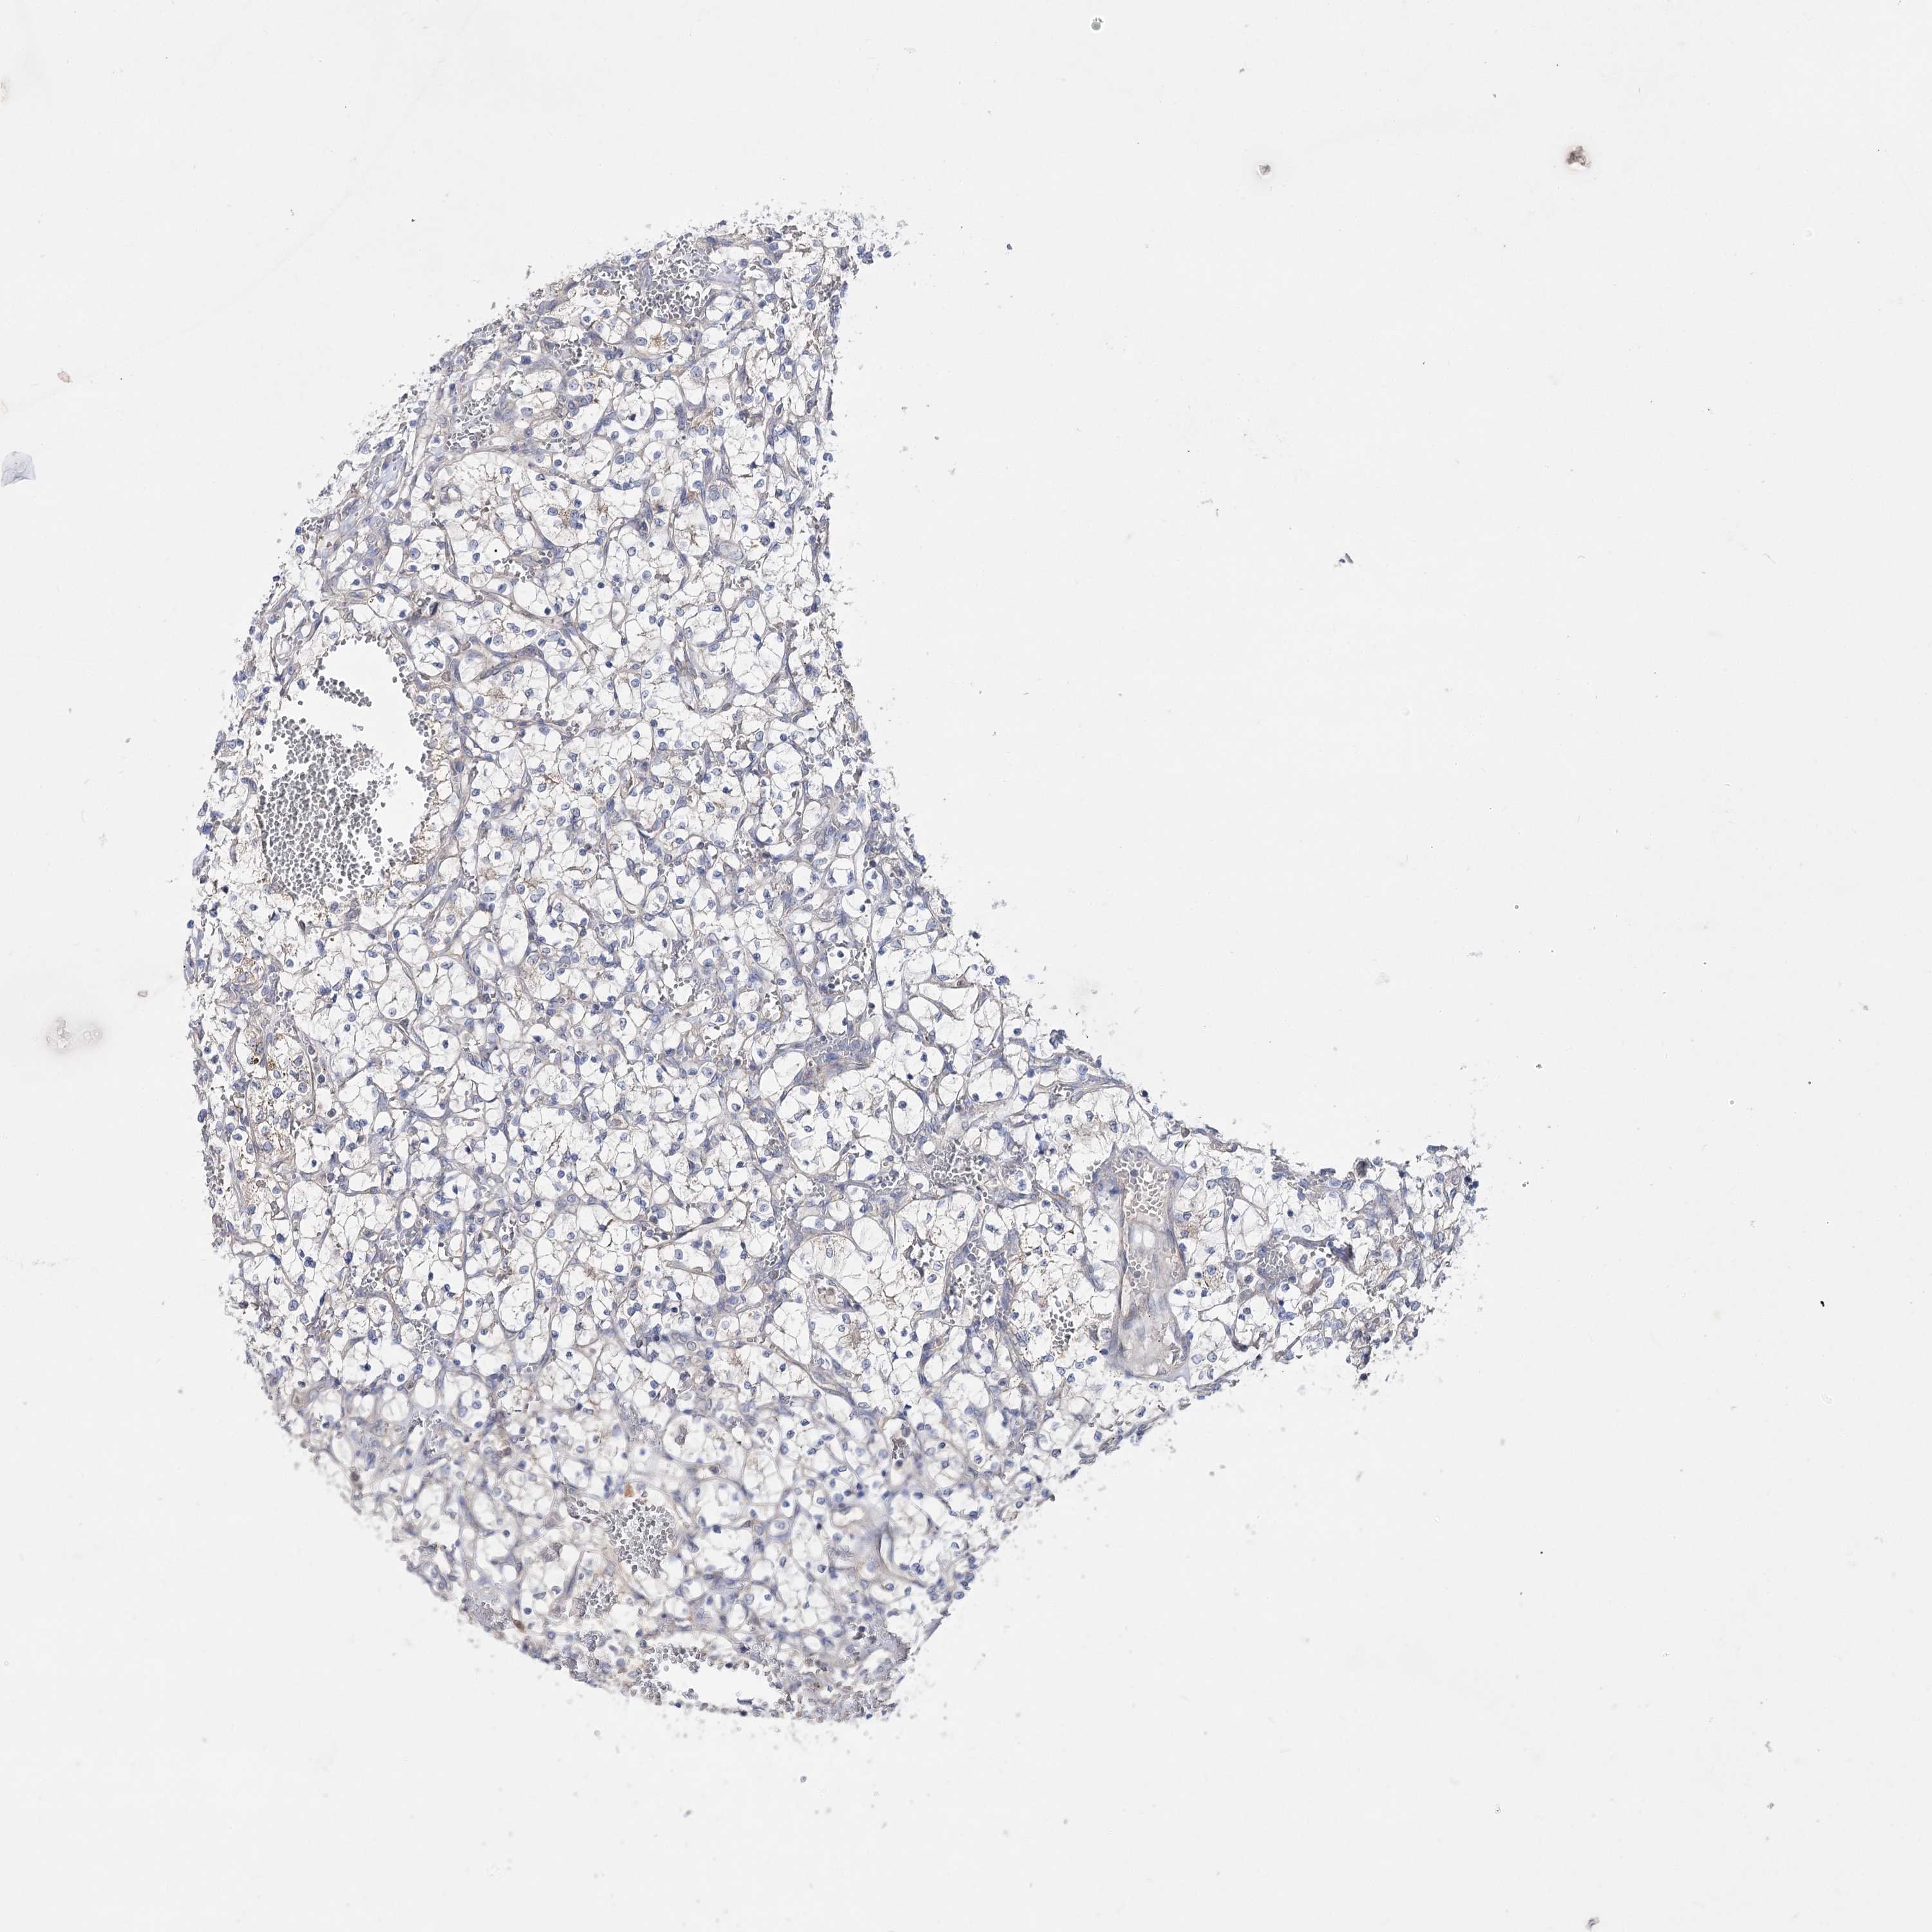

KIDNEY RENAL CLEAR CELL CARCINOMA (VALIDATION) - Interactive survival scatter ploti

The Survival Scatter plot shows the clinical status (i.e. dead or alive) for all individuals in the patient cohort, based on the same data that underlies the corresponding Kaplan-Meier plots. Patients that are alive at last time for follow-up are shown in blue and patients who have died during the study are shown in red.

The x-axis shows the expression levels (FPKM) of the investigated gene in the tumor tissue at the time of diagnosis. The y-axis shows the follow-up time after diagnosis (years). Both axes are complimented with kernel density curves demonstrating the data density over the axes. The top density plot shows the expression levels (FPKM) distribution among dead (red) and alive patients (blue). The right density plot shows the data density of the survived years of dead patients with high and low expression levels respectively, stratified using the cutoff indicated by the vertical dashed line through the Survival Scatter plot. This cutoff is automatically defined based on the FPKM cutoff that minimizes the p-score. The cutoff can be changed by dragging the vertical line or by entering a cutoff value in the square labeled "Current cut-off".

Under the Survival Scatter plot the p-score landscape (black curve; left axis) is shown together with dead median separation (red curve; right axis). Dead median separation is the difference in median mRNA expression between patients who have died with high and low expression, respectively. It is calculated as follows: median FPKM expression of dead patients with high expression - median FPKM expression of dead patients with low expression. This is intended to aid the user in visually exploring custom cutoffs and the associated p-scores and dead median separation.

Individual patient data is displayed and can be filtered by clicking on one or more of the category buttons on the top of the page. Categories describing expression level and patient information include: high, low, alive, dead, female, male and tumor stages. The scale of the x-axis can be toggled between linear and log-scale by clicking on the "x log" button. Mouse-over function shows TCGA ID, patient information and mRNA expression (FPKM) for each patient.

& Survival analysisi

Kaplan-Meier plots summarize results from analysis of correlation between mRNA expression level and patient survival. Patients were divided based on level of expression into one of the two groups "low" (under cut off) or "high" (over cut off). X-axis shows time for survival (years) and y-axis shows the probability of survival, where 1.0 corresponds to 100 percent.

AURKC is not prognostic in Kidney Renal Clear Cell Carcinoma (validation)

Best expression cut offi

Based on the FPKM value of each gene, patients were classified into two groups and association between prognosis (survival) and gene expression (FPKM) was examined. The best expression cut-off refers the FPKM value that yields maximal difference with regard to survival between the two groups at the lowest log-rank P-value. Best expression cut-off was selected based on survival analysis .

When clicking on this number, the vertical dashed line indicating cut-off, the interactive survival plot, and the Kaplan-Meier curve will be adjusted to show results based on the best expression cut-off.

: 2.35

P scorei

Log-rank P value for Kaplan-Meier plot showing results from analysis of correlation between mRNA expression level and patient survival.

N/A

TCGA RNA samplesi

RNA-seq data is reported as average FPKM (number Fragments Per Kilobase of exon per Million reads), generated by the The Cancer Genome Atlas (TCGA) .

Normal distribution across the dataset is visualized with box plots, shown as median and 25th and 75th percentiles. Points are displayed as outliers if they are above or below 1.5 times the interquartile range. FPKM values of the individual samples are presented next to the box plot.

Average pTPM 1.8

Number of samples 100